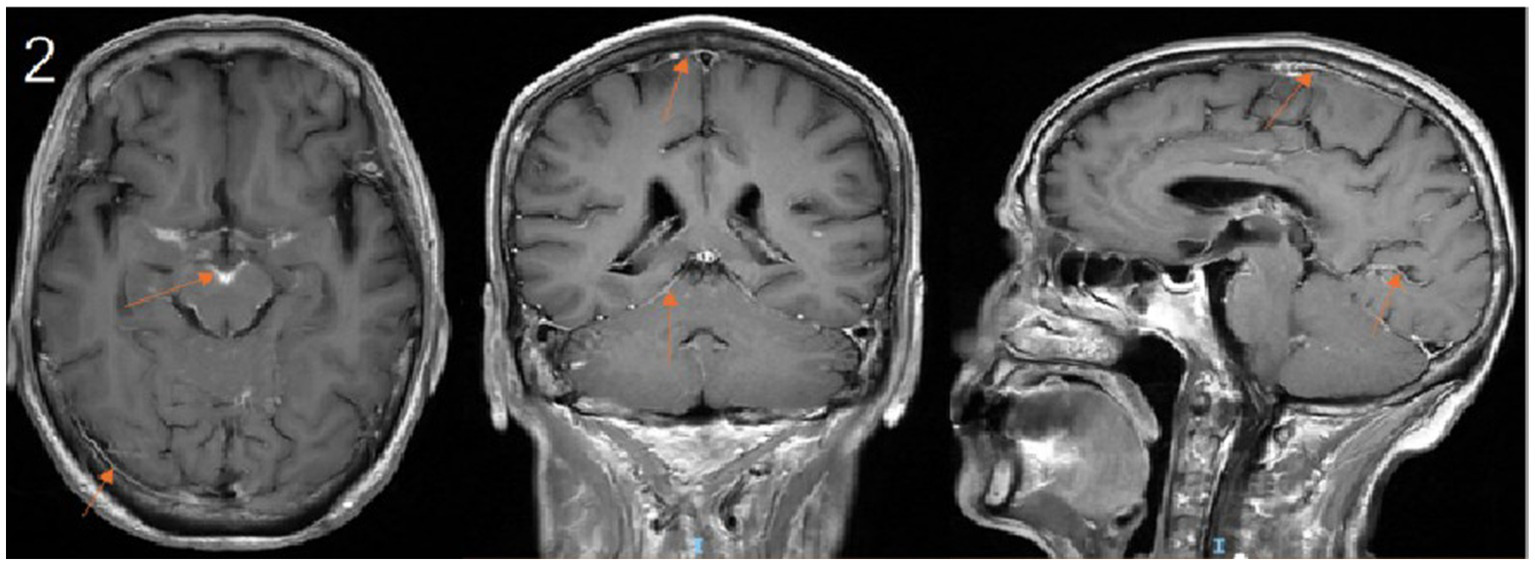

Upon transfer to our department, the existing anti-infective regimen was maintained, and a comprehensive diagnostic workup was initiated. Cranial MRI demonstrated multiple areas of leptomeningeal enhancement (Figure 2). Lumbar puncture revealed an elevated opening pressure of 240 mmH₂O. CSF analysis showed marked pleocytosis, elevated protein, and decreased glucose and chloride levels. Cytological examination identified abundant small lymphocytes, suggestive of CNS involvement by lymphoma (Table 2). mNGS of the CSF detected microbial genomes corresponding to Cryptococcus neoformans (77.78% relative abundance) and Pseudomonas aeruginosa (28.57% relative abundance). No pathogenic autoantibodies associated with autoimmune encephalitis were detected. Additionally, CSF smear confirmed the presence of Cryptococcus neoformans, and the CrAg was positive.

Figure 2. Contrast-enhanced cranial MRI demonstrates leptomeningeal enhancement along the sulci and cisterns. (arrows).